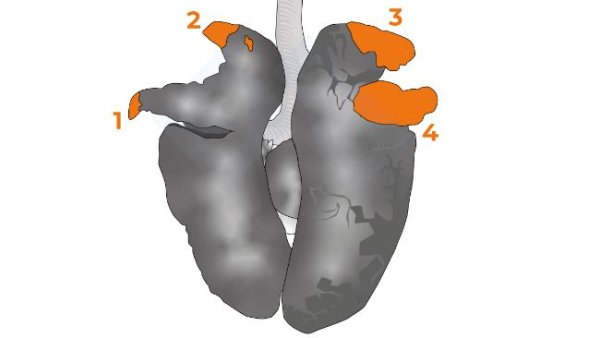

En la cuarta entrega del manual abordamos el examen de los órganos de la cavidad torácica.